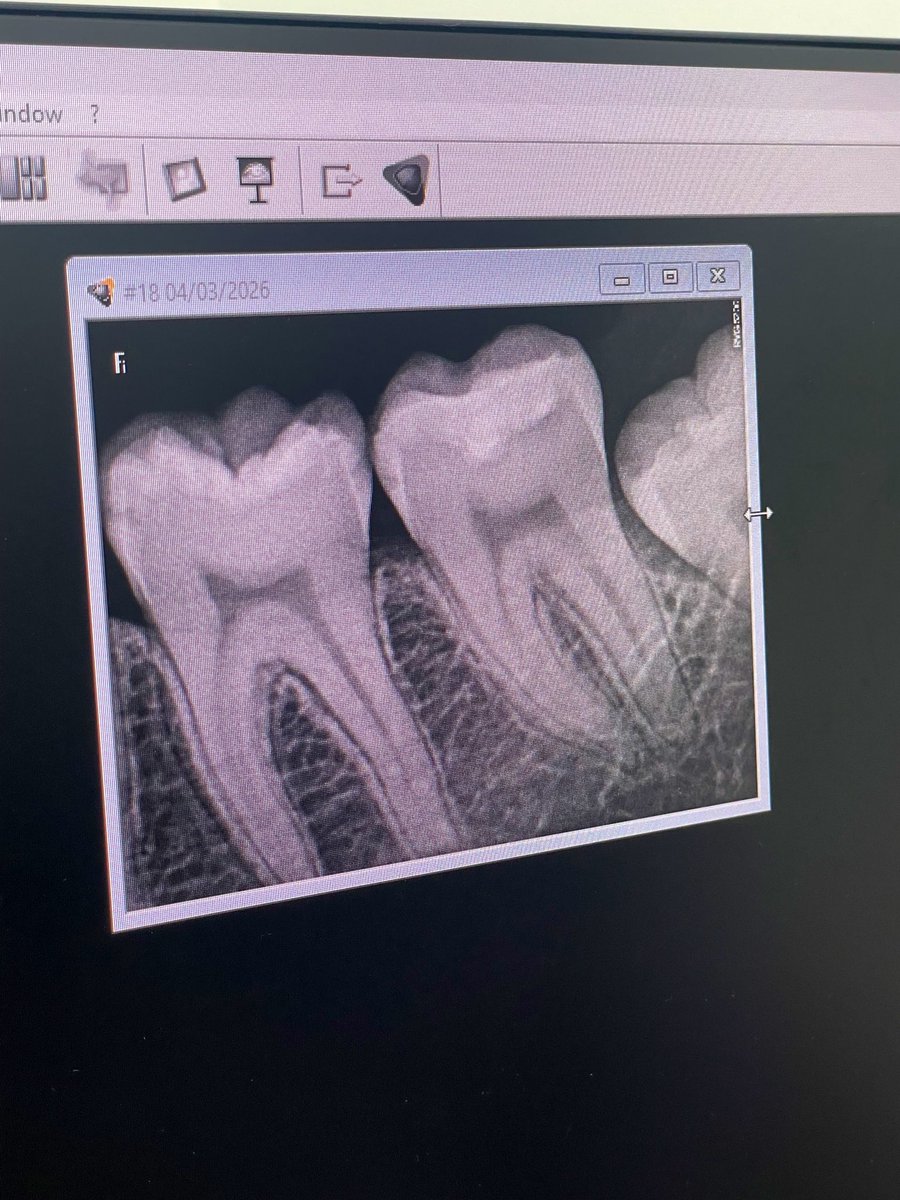

Intern Case Report – Endodontic Management of Tooth #22 with Periapical Abscess حضرت المريضة لاستكمال Endodontic treatment للسن رقم (22)، وكانت تعاني سريريًا من Periapical abscess مصحوب بأعراض ألم وتنميل. تم تحديد وتأكيد Working Length (WL) وبلغ 19.5 mm عند إجراء Canal negotiation تبيّن أن القناة Narrow canal، وعليه تم البدء بمرحلة Cleaning and Shaping باستخدام Hand files بشكل تدريجي حتى مقاس #35 بهدف إنشاء Glide Path آمن يسهّل إدخال الأدوات ويقلل من احتمالية حدوث Canal transportation أو Ledge formation أو Instrument separation. تم إجراء irrigation بصورة مستمرة خلال جميع مراحل التحضير لتعزيز Debridement وتقليل البكتيريا داخل القناة الجذرية. بعد تحقيق Preliminary enlargement مناسب، تم إدخال Rotary instrumentation ابتداءً من مقاس #20 لاستكمال Biomechanical preparation مع المحافظة على المسار التشريحي الأصلي للقناة. في نهاية الجلسة تم وضع Composite filling لضمان Coronal seal ومنع Reinfection .